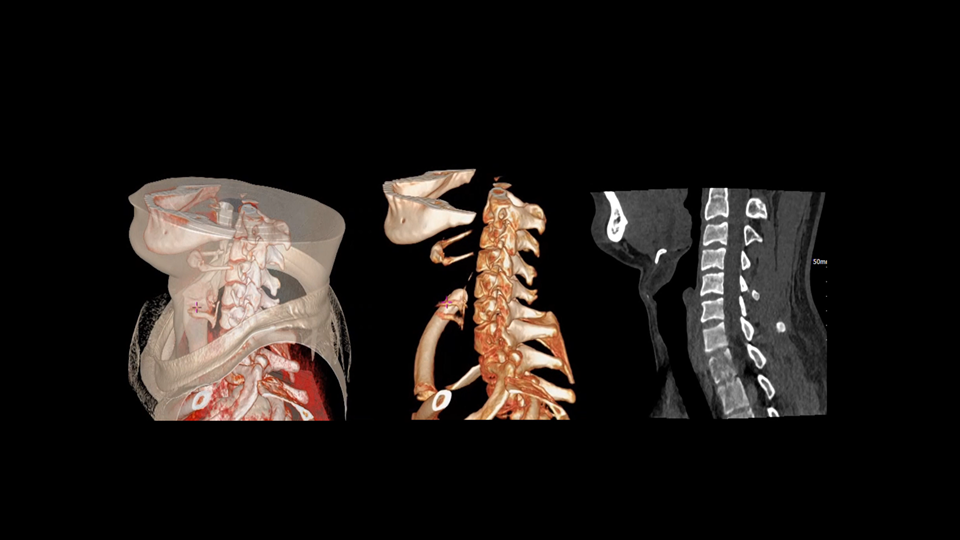

uCT SiriuX® 以全新双宽体系统架构,同步实现超高时间分辨率与宽体容积覆盖兼得,全面释放性能潜能,敏锐捕捉人体生理运动全景,带来动态影像新视角。

巅峰系统形态

双宽体“零”噪声时空探测器,Z 方向覆盖达16 cm,单圈即可完整扫描头颅、心脏等关键器官,结合超高时间分辨率,可实现真正意义上的全身各部位高清动态成像,让每一次扫描都更高效、更精准。

uCT SiriuX® 以16cm超宽Z轴覆盖,使超高时间分辨率应用于完整器官成像。无论是心脏搏动还是关节运动,整个目标区域可在同一瞬时被完整、清晰地捕捉,彻底消除时序误差,实现从“局部瞬间”到“全器官瞬时”的成像跨越。

全身各部位动态CT成像